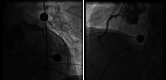

Results: In comparison with the pre-outbreak period, patients during the outbreak period were older (59.6 ± 12.9 vs. 62.6 ± 12.2, p = .03) with a delayed seek to care (mean delay first symptoms-balloon 3.8 ± 3 vs. .7.4 ± 7.7, p < .001) resulting in a two-fold higher in-hospital mortality (non COVID-19 4.3% vs. COVID-19 8.4%, p = .07). Among the 83 STEMI patients admitted during the outbreak period, 11 patients were infected by COVID-19. Higher biological markers of inflammation (C-reactive protein: 28 ± 39 vs. 98 ± 97 mg/L, p = .04), of fibrinolysis (D-dimer: 804 ± 1,500 vs. 3,128 ± 2,458 μg/L, p = .02), and antiphospholipid antibodies in four cases were observed in the COVID-19 group. In this group, angiographic data also differed: a thrombotic myocardial infarction nonatherosclerotic coronary occlusion (MINOCA) was observed in 11 cases (1.4% vs. 54.5%, p < .001) and associated with higher post-procedure distal embolization (30.6% vs. 72.7%, p = .007). The in hospital mortality was significantly higher in the COVID-19 group (5.6% vs. 27.3%, p = .016).

Conclusion: The COVID-19 outbreak implies deep changes in the etiopathogenesis and therapeutic management of STEMI patients with COVID-19. The impact on early and long-term outcomes of systemic inflammation and hypercoagulability in this specific population is warranted.